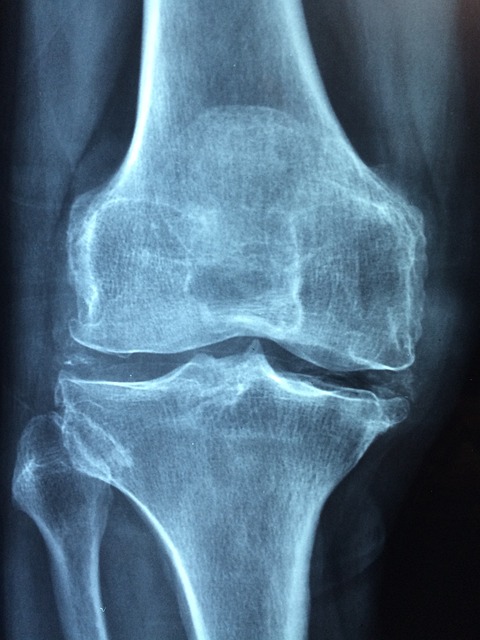

우슬의 뿌리는 대체 의학에서 주로 치료제로 활용되며, 특히 류머티즘, 관절염, 강직성 척추염과 같은 질환의 증상을 완화하는 데 효과적인 것으로 여겨집니다. 이 식물은 동의보감과 같은 전통 의학 서적에도 자주 언급되며, 그 효능으로 인해 많은 사람들이 관심을 가지고 있습니다.

- 항염증 효과: 우슬의 사포닌 성분은 체내의 염증 반응을 조절하여 염증을 감소시키는 데 도움을 줍니다. 이로 인해 관절염, 강직성 척추염 등 염증성 질환의 증상 완화에 기여할 수 있습니다.

- 진통 효과: 우슬에 함유된 알칼로이드는 자연적인 진통제 역할을 하여 다양한 유형의 통증, 특히 관절 및 근육 통증을 완화하는 데 효과적입니다. 이는 운동 후 회복을 촉진하거나 만성 통증 관리에 유용할 수 있습니다.

- 골다공증 예방: 연구에 따르면, 우슬은 뼈의 밀도를 증가시키고 골 손실을 방지하는 데 도움을 줄 수 있습니다. 이는 골다공증이나 다른 뼈 관련 질환을 예방하거나 관리하는 데 유익할 수 있습니다.